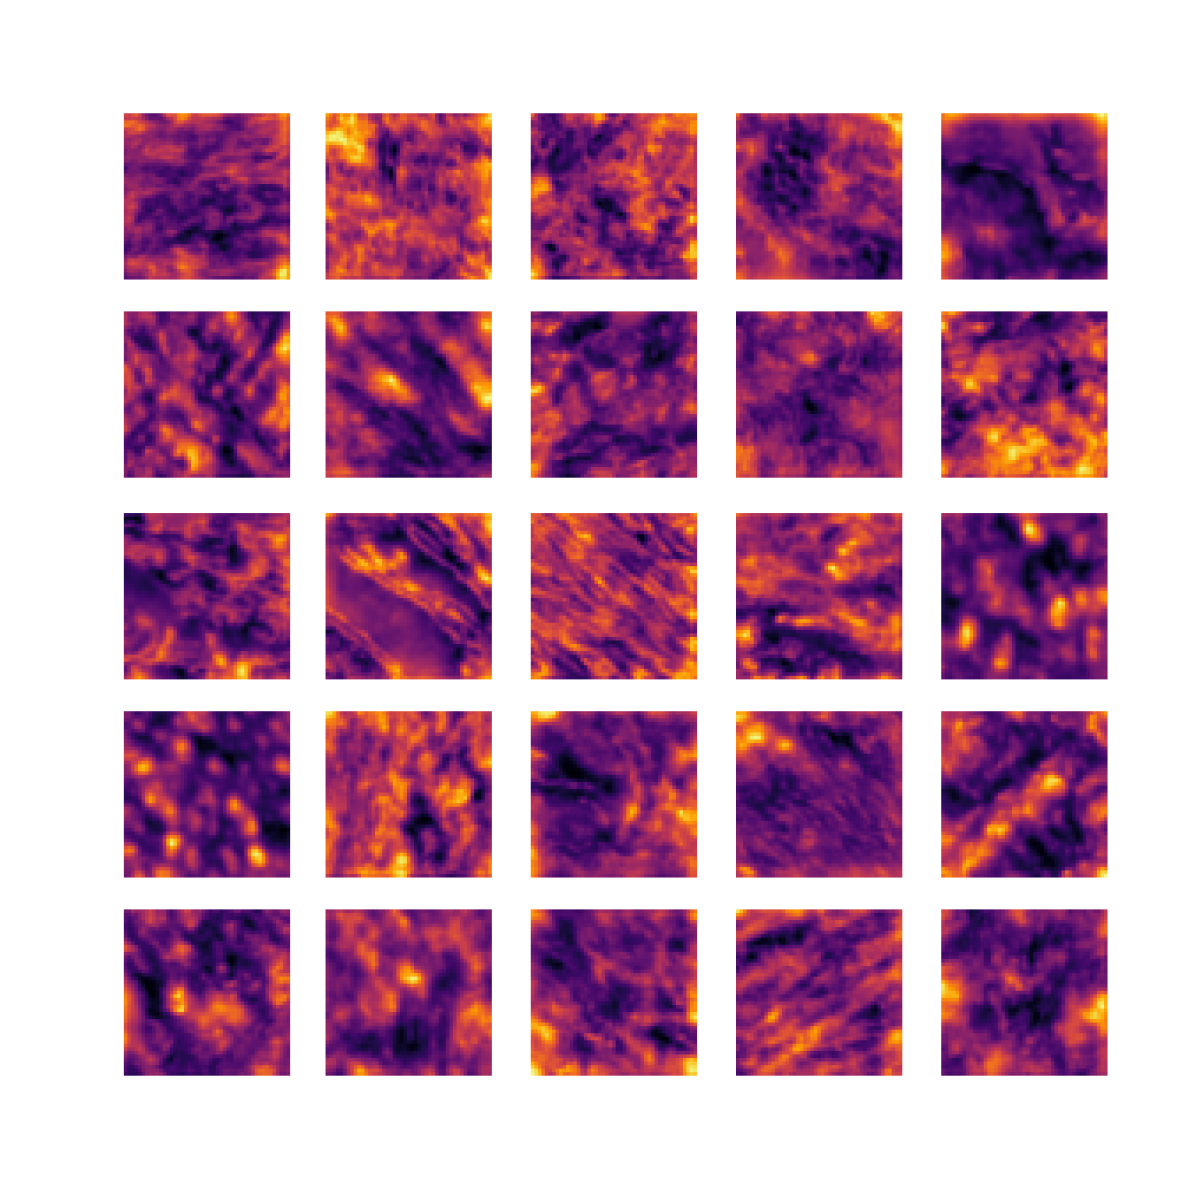

We also analyse the activation maps for each model using GradCAM as described in section S3. This offers more insight into the areas of the image which are contributing most heavily to the models’ representations. In Figure 4(b) we present some representative examples, however, a larger selection which was chosen at random is presented in Figures S10 to S25. The larger selection makes it easier to see the emergent patterns, including that privileged Siamese models tend to mainly identify features which are strongly present in both inputs, while unprivileged Siamese models tend to learn more diffuse features that are not specific to one cell phenotype or image region. TriDeNT ♆ incorporates both sets of features, learning both features specific to the privileged data and more the general features associated with unprivileged Siamese networks.

We can see in Figure 4(b) panel A that for ERG, the privileged Siamese model focuses almost exclusively on any nuclei which could be endothelial cells. As there are very few endothelial cells in the dataset, it could be an effective strategy to identify anything that could potentially be an endothelial cell to minimise the difference between the representations of the H&E model and the IF mask model. In the corresponding unprivileged Siamese image, we see that the model identifies some of these nuclei, albeit less strongly, but also focuses heavily on the other tissue and even the background, while strongly fixating on two spots of debris in the center of the image. This model has less ‘incentive’ to learn the weak features related to endothelial cells as these occur rarely and are not easy to detect, while more generic strong features such as the presence of connective tissue and the prevalence of background are more common and predictable from augmented images. We see that TriDeNT ♆ combines these two feature sets, strongly identifying nuclei while also identifying the connective tissue.

In panel C we see a similar pattern, with the privileged Siamese model fixating solely on the nuclei, while the TriDeNT ♆ model takes a more balanced approach. The unprivileged Siamese model appears to focus on a single cluster of nuclei while neglecting others, and similarly identifies an area of fibroblasts with its distinctive pattern but does not others.

In contrast to panels A and C which represent models with poor privileged Siamese results, panels B and D represent models whose privileged Siamese results were comparable to both TriDeNT ♆ and even the supervised baseline. It is therefore interesting to note that there are far more similarities between the privileged Siamese and TriDeNT ♆ models in both cases. Particularly in panel B, TriDeNT ♆ and the privileged Siamese model return virtually identical heatmaps, with both strongly identifying epithelial nuclei and neglecting the same areas of connective tissue. The unprivileged model in this case appears to focus solely on the centre of the image, giving a significantly different heatmap to the other panels.

Panel D again shows the previous pattern, with the privileged Siamese model identifying the features strongly present in the privileged data – fibroblasts – while neglecting the nuclei present. TriDeNT ♆ also strongly identifies the connective tissue, but, unlike the privileged Siamese model, does not completely neglect the nuclei. The unprivileged Siamese model primarily identifies background, and does not appear to identify the nuclei in this example.